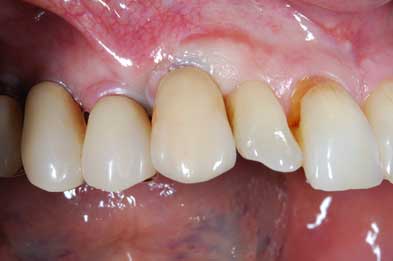

Con protesi fissa superiore e protesi fissa inferiore

I denti irrecuperabili dell'arcata superiore ed inferiore del paziente di anni 65

sono stati sostituiti da 10 impianti, cioè protesi radicolari endo-ossee che sostengono le protesi fisse superiore ed inferiore.